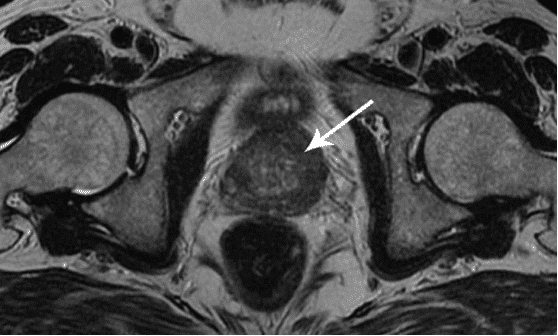

Rak prostate kod muškarca starog 58 godina. Uzrok - dugotrajna apstinencija (od 51 godine). Pacijent je preminuo.